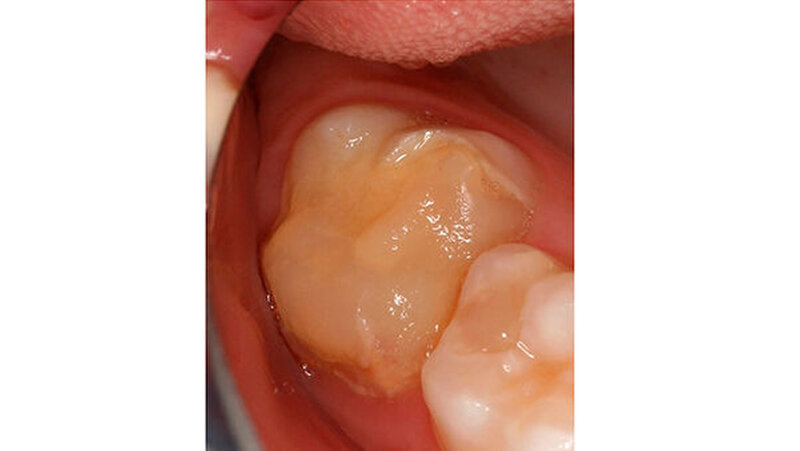

Wie im Fall zur Füllungstherapie ausführlich beschrieben, ist der Haftverbund der derzeit verfügbaren Materialien aufgrund des hypomineralisierten Schmelzes in der Regel nicht zufriedenstellend und oft von einem frühzeitigen Füllungsverlust und/oder einem weiteren Einbruch in den an die Restauration angrenzenden Bereichen begleitet (Abbildungen 9 und 10).

Je nach Größe des eingebrochenen Defekts werden folgende Optionen – in Abhängigkeit von Alter des Patienten, Lokalisation und Schweregrad der betroffenen Zähne und Anästhesierbarkeit - für den Seitenzahnbereich empfohlen:

Temporäre Versorgung mit Glasionomerzement: Insbesondere in schlecht trocken zu legenden Bereichen kann ein Glasionomerzement eine vorübergehende Lösung darstellen. Hinzu kommen die Bindung an Schmelz und Dentin und Fluoridabgabe. Da bei MIH-Zähnen aber oft die Kaulast tragenden Bereiche betroffen sind, sind Glasionomerzemente wiederum als eher ungeeignet einzustufen und werden deshalb nur als vorübergehende Therapieoption empfohlen (Abbildung 11).

Für kleine und mittelgroße Defekte sind Komposite sehr gut geeignet. Wenig kann zu der Verwendung eines geeigneten Adhäsivsystems gesagt werden, aus einer knapp zehn Jahre alten Untersuchung geht hervor, dass self-etch Systeme möglicherweise den total-etch Systemen überlegen sein können, weil es hier nicht mehr zu Interferenzen nach dem Abspülen kommt. Die größte Schwierigkeit besteht hierbei aber, dass für eine akzeptable Haltbarkeit dieser Restaurationen gefordert wird, die Kavitätenränder in gesunden Schmelz zu legen. Aufgrund des Umfanges der Läsionen sind die Voraussetzungen für diese Maßnahme nur selten erfüllt (vgl.Fallbeispiel auf zm-online). (Abbildung 12).